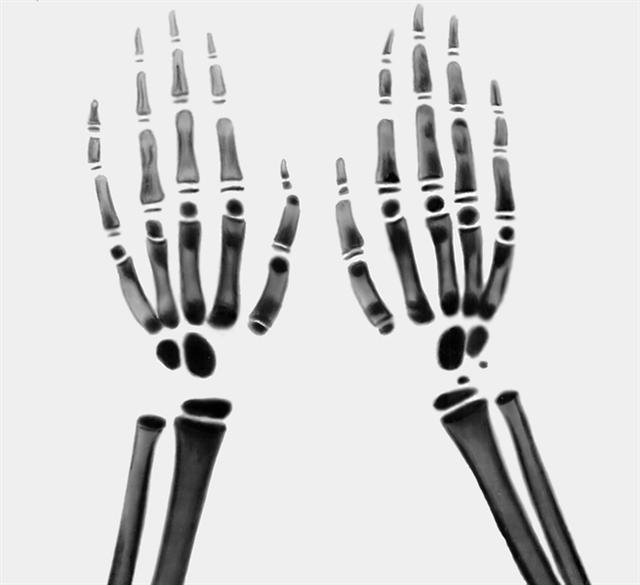

Рис. в). Рентгенограмма кистей рук и части предплечий при врожденной мраморной болезни: избыточное развитие компактного вещества, очаги склерозирования костной ткани и уплотнение ее структуры в различных костях скелета.